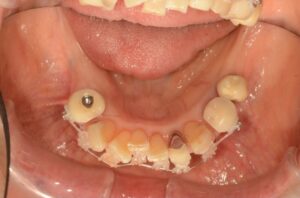

Before

| 治療方法 | 歯と歯の間に0.5mmのやすりがけをして歯の横幅を修正し、マルチブラケット装置(ワイヤー矯正器具)にて歯を配列 |

叢生(歯並びのガタつき)が気になるとのことで、矯正治療をスタートしました。